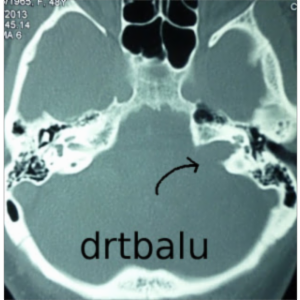

This is a site that has a great deal of material on it. According to the author, "This site is intended to give study material and tutorials for students. This is a free site. The topics are presented under three heads, Otology, Rhinology and Laryngology. Where ever available multiple choice questions are provided in flash format. You are welcome to test your knowledge and understanding of the subject." There are also surgical videos that can be...